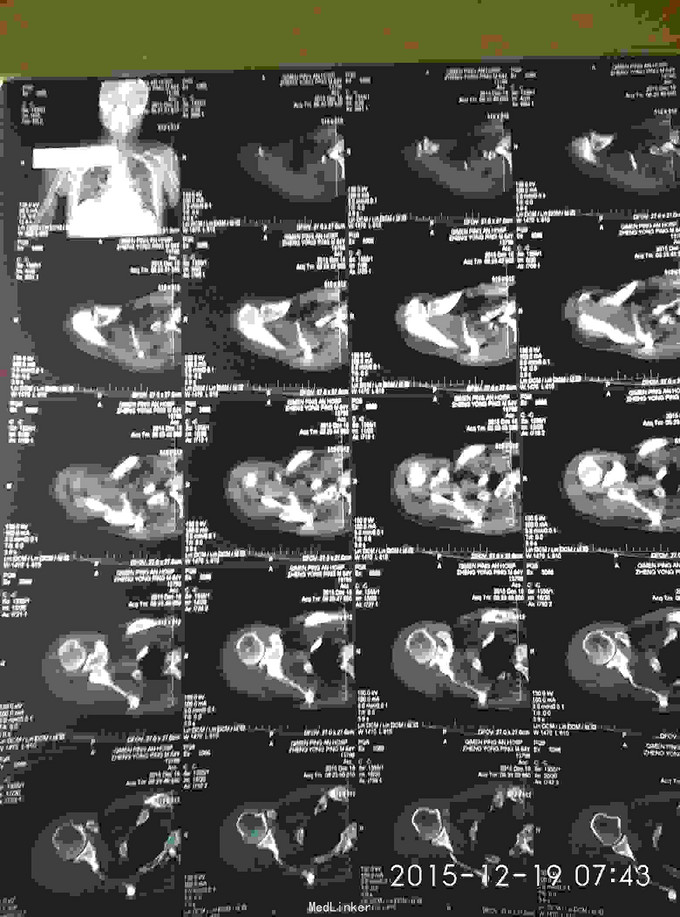

右肩峰及肩胛骨骨折

骨折 肩峰骨折 肩胛骨骨折

外伤致右胸疼痛及右肩疼痛,活动受限1天入院。去年右肩胛骨骨折在外院行切开复位内固定术。

胸廓挤压试验阳性,右肩峰压痛阳性,右肩主动活动受限,外展约30度。x片及CT示右肩峰骨折及肩胛骨骨折,右第6.7.8.9肋骨骨折。

右肩峰骨折,右肩胛骨骨折,右第6.7.8.9肋骨骨折